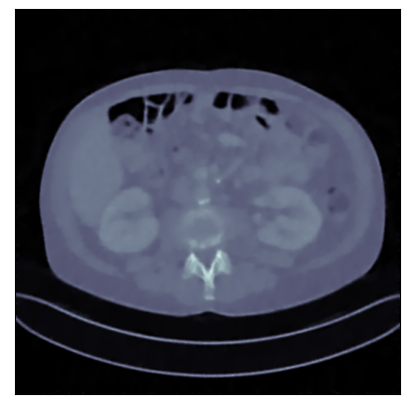

Refer to captionRefer to caption

Ground-truth

FBP: 21.303 dB, 0.195

TV: 31.690 dB, 0.889

U-Net: 36.712 dB, 0.920

LPD: 36.810 dB, 0.912

AR: 36.694 dB, 0.907

ACR: 35.708 dB, 0.897

ACNCR: 36.533 dB, 0.921

AWCR: 37.603 dB, 0.918

AWCR-PD: 37.941 dB, 0.924

Figure 2: Reconstructed images obtained using different methods, along with the associated PSNR and SSIM, for sparse view CT. In this case the AWCR and AWCR-PD achieve the highest PSNR and SSIM. Furthermore, both AWCR methods retain the fine-structure in the reconstruction, unlike the ACNCR and ACR, the only other methods which possess convergence guarantees.

These comparisons illustrate the trade-offs in levels of constraints and supervision versus stability and performance. For details of the experimental set-up, see Section G.1. We measure the performance in terms of the peak signal-to-noise ratio (PSNR) and the structural similarity index (SSIM) [Wang et al., 2004]. We report average test dataset results in Table 1, with further visual examples in Figure 2.

Sparse view CT As in [Lunz et al., 2018] performance of AR during reconstruction begins to deteriorate if the network is over-trained, so early stopping must be employed in training. For the ACR, ACNCR, and both AWCR methods this does not occur due to reduced expressivity, yet both AWCR methods surpass the performace of AR. Indeed, the AWCR-PD method approaches the PSNR accuracy of the strongly supervised U-Net post-processing method.